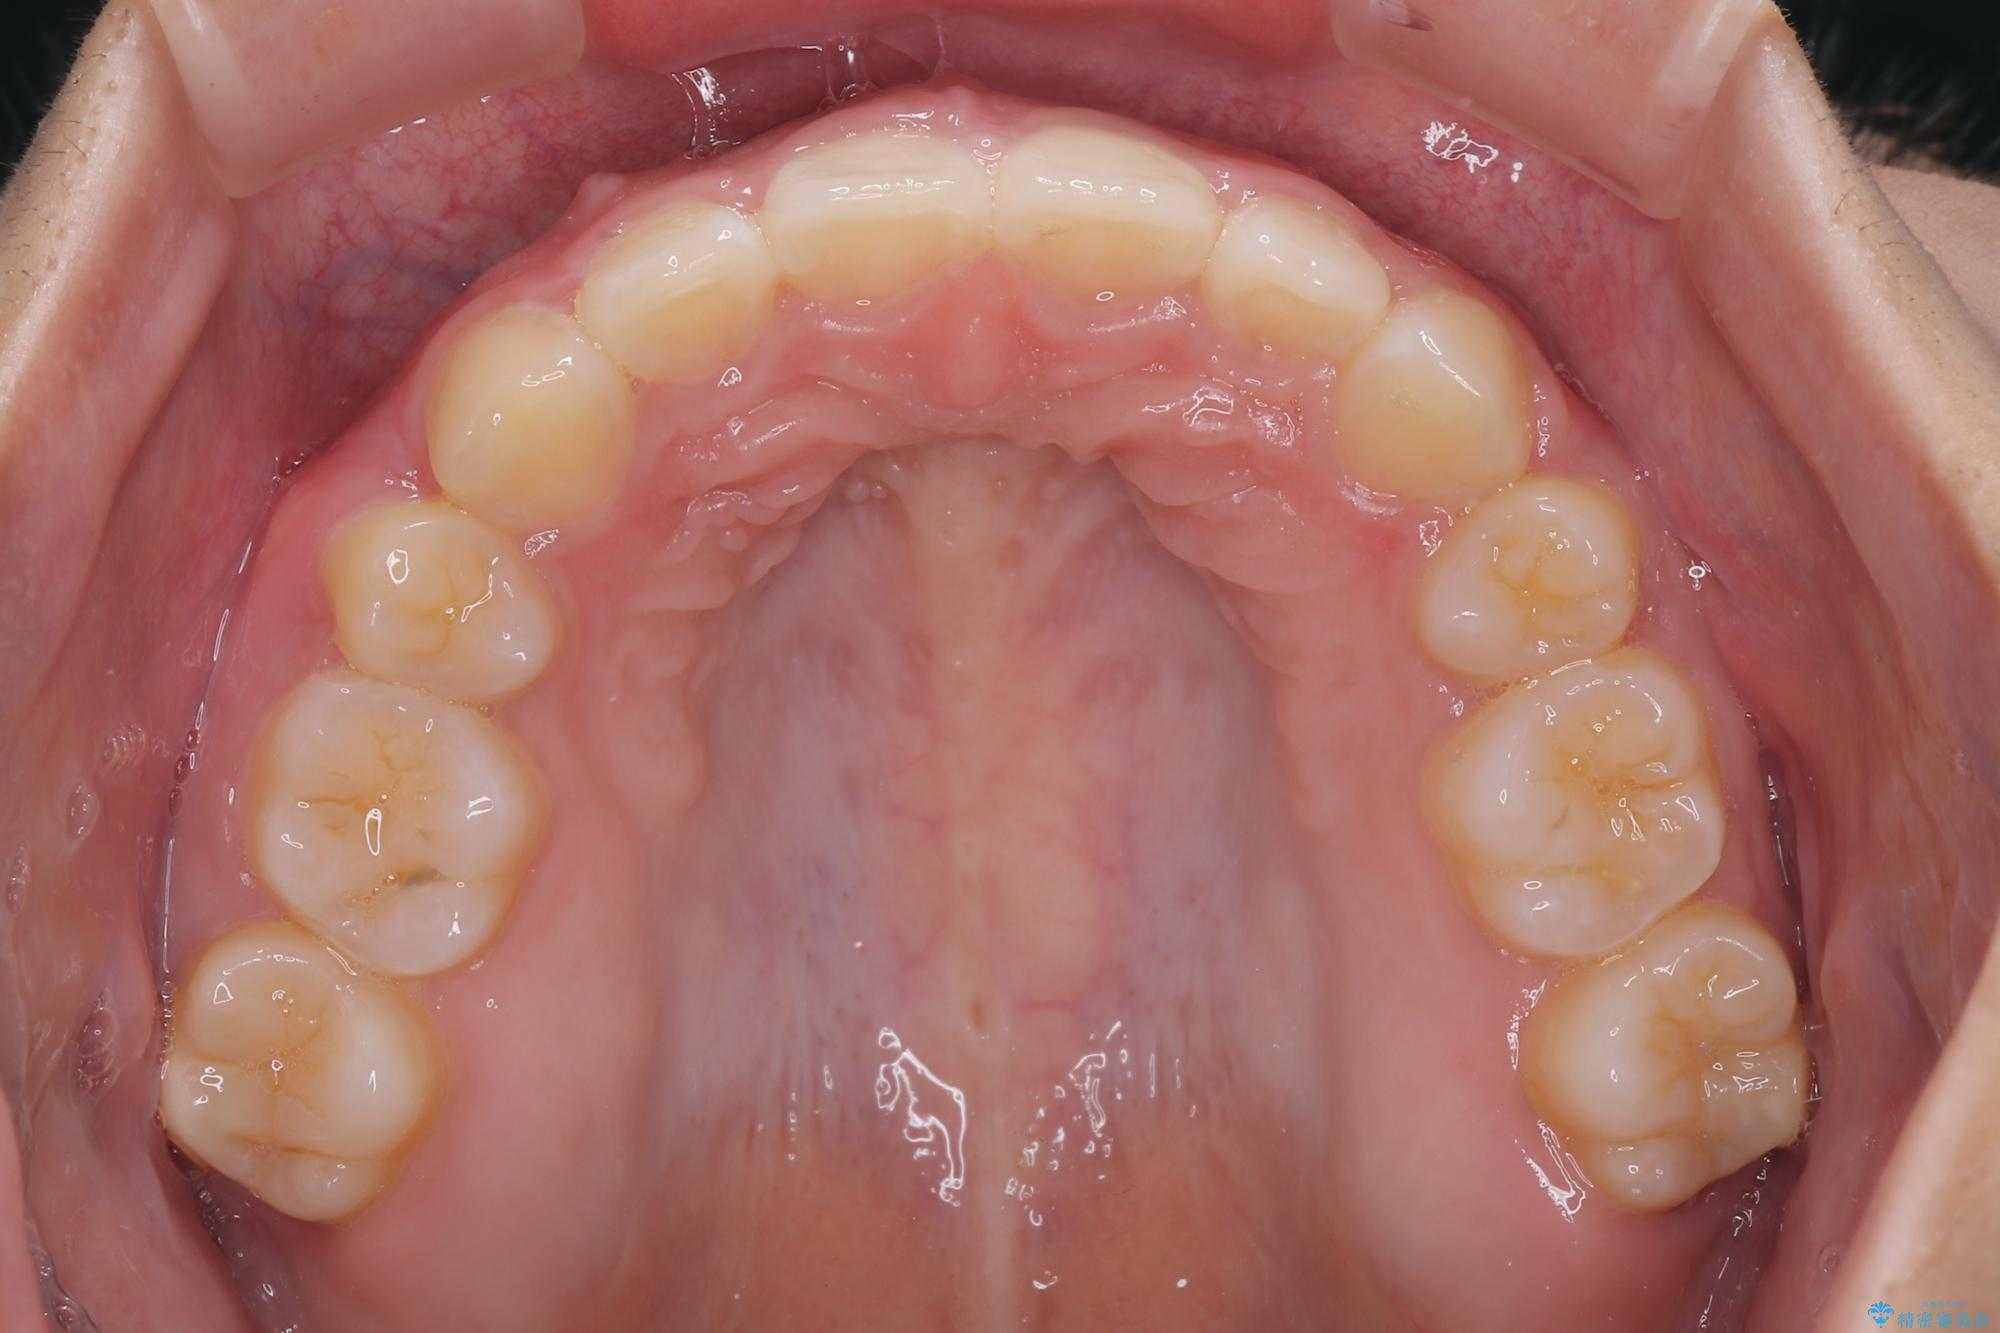

- 上顎前歯が飛び出していて唇がうまく閉じられないとのことで来院された患者様です。

くちばしのように前歯が突出していたため、口元を積極的に引っ込めるために、上下左右の小臼歯4本を抜歯することとしました。

また、上顎歯列が下顎に対して前方位に位置していたため、補助装置を用いて上顎歯列を後方に移動させ、より積極的に口元を下げるようにしました。

上下正中位置を改善するため、左下はイレギュラーに第二小臼歯を抜歯しました。そのため治療期間の長期化が予想されましたが、2年半ほどで期待通りの歯列に仕上げることができました。